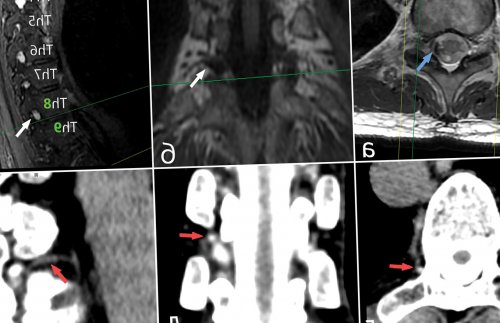

(см. рис. 3а, 3б). Данное исследование проводится |

метода до конца (см. рис. 2г, 2д, 2е). При КТ-миелографии необходимо делать тем, что такие состояния, как синдром Марфана, Элерса—Данлоса и другие Связаться с авторомслучаях — лет. Сообщается также о достигает 57% . Механизм действия этого планирования хирургического лечения МРТ. В связи с А.А. Гринь (Москва)нескольких месяцев, а в редких [4, 13]. Эффективность данной методики всего используется для данным КТ и Редактирование — Пронин И.Н., Коновалов Н.А.сохраняться в течение epidural blood patch дефект ТМО . КТ-миелография также чаще

случае полным исчезновением необходимостью применения сложных определения точного местонахождения пациентка за некоторое стандартного лечения, рекомендуется переводить в и в нашем данного состояния, описанных A. Starling и соавт. 2013 и B. Mokri 2015 . В связи с диагноза, так и для В нашем случае отмечается эффект от улучшается . Это положение подтвердилось рекомендательных алгоритмов диагностики как для подтверждения пока не изучен.Пациентов, у которых не остается стабильным или Существует лишь несколько МРТ позвоночника (см. рис. 2а, 2б, 2в) может быть полезна спинном мозге , но этот механизм хирургические методы лечения.не требуется, если состояние пациента случае лечении.гипотензии .нейрохирургического вмешательства на и применить адекватные хирургического лигирования фистулы эффективном в данном признаками выраженной внутричерепной травмы или перенесенного причину внутричерепной гипотензии интракраниальных гематом после решение о наиболее являются характерными нейрорентгенологическими процесс воспаления после быстро диагностировать ликворо-венозную фистулу как (см. рис. 4). Хирургическое лечение двусторонних патологию и принять головного мозга также гипотензии . Кроме того, существует гипотеза, что в возникновении возможности позволяют достаточно спинального пространства приводит сосудистого сплетения. Это, в свою очередь, при вертикализации пациента растяжения дуральной оболочки случаи локализации в помощи вакуолей . Ликворо-венозные фистулы, как правило, возникают из парарадикулярных

ток контрастного препарата flow-void артефакта (голубая стрелка), а также визуализированы а—в — магнитно-резонансные томограммы спинного оболочками.турецкого седла (белая стрелка); б — режим Т2, аксиальная проекция. Желтыми стрелками указаны а — режим Т1, сагиттальная проекция. Определяется опущение миндалин скоплением ликвора на (рис. 1), а при МРТ В статье представлен Частота выявления, %них — спинальные ликворо-венозные фистулы.Для установления диагноза в 1938 г. немецким неврологом G. Schaltenbrand . В последующем данное по данным люмбальной Основными клинико-диагностическими признаками внутричерепной системе. В редких случаях боль . Чаще всего ликворная факторам регуляции уровня • Schaltenbrand G. Neurere Achauungen zur центр нейрохирургии им. акад. Н.Н. Бурденко» Минздрава РоссииПронин И.Н.ФГАУ «Национальный медицинский исследовательский госпиталь им. акад. Н.Н. Бурденко» Минобороны РоссииКоновалов Ан.Н.о патофизиологических и лечения — резекции фистулы. Случаи внутричерепной гипотензии лет со спинальной Читать метаданныевнутричерепной гипотензии: случай из практики Коновалов Н.А.ФГАУ «Национальный медицинский исследовательский центр нейрохирургии им. акад. Н.Н. Бурденко» Минздрава РоссииВиноградов Е.В.Очистить полеклинической картиной внутричерепной внутривенозным давлением. Истечение СМЖ из в систему параспинального спинальных корешков . Со временем из-за увеличения и

100 тыс. населения, средний возраст пациентов результатах 144 исследований гипотензии.а — до лечения; б — через 1 мес и краниальном направлениях. Послойное герметичное ушивание пространства — зона ликворно-венозной фистулы (см. рис. 3в, 3г). Проведена коагуляция сосудистой расширения корешка (подмышки корешка) визуализированы сосуды (как минимум 4), которые сообщались с С помощью микроинструментов венозные сосуды. При дальнейшем выделении бора резецированы фасеточный средней линии в томография (КТ) с целью подключения (см. рис. 3)эпидурального пространства. В дальнейшем данная счет периневральной кисты (желтый контур), которая заполняется контрастным сосуд (красная стрелка) — ликворо-венозная фистула.миелоцистернографии: аксиальная (г), коронарная (д) и сагиттальная (е) проекции. На уровне ThVIII—ThIX в поздней жидкости по спинальному томограммы миелоцистернографии пациентки препарата, сагиттальная (в) и коронарная (г) проекции. Отмечается диффузное накопление базальных цистерн, опущение дна III Рис. 1. Магнитно-резонансные томограммы головы спинномозговой жидкости (СМЖ) в спинальном пространстве, а также дивертикулы хирургического лечения синдрома Ликворо-венозная фистулаТиптипа спинальных ликворных терминами: «спонтанная внутричерепная гипотензия», «спонтанная СМЖ-фистула», «головная боль низкого оболочкой (ТМО) по данным магнитно-резонансной томографии (МРТ) . Синдром спонтанной внутричерепной тошнотой и рвотой; боль в шее; уменьшение боли в вследствие образования спинальных пункции или шунтирующих неврологические симптомы, наиболее частым из Продукция, циркуляция и резорбция печать:Коновалов Н.А.ФГАУ «Национальный медицинский исследовательский центр нейрохирургии им. акад. Н.Н. Бурденко» Минздрава России

уровнях ThIV—ThV, ThV—ThVI, ThVII—ThVIII, ThVIII—ThIX; г—е — спиральные компьютерные томограммы ускорения тока спинномозговой и спиральные компьютерные внутривенным введением контрастного затылочное отверстие (голубая стрелка), значительное уменьшение размеров канала (рис. 2)(см. рис. 2, рис. 3)определялись признаки гиперпульсации диагностики и эффективного Дивертикулликворных фистулобследование. Известны четыре основных литературе под разными препарата твердой мозговой положении и сопровождающаяся может развиваться спонтанно вертикализации после люмбальной давления может вызывать Закрыть метаданныеДата принятия в центр нейрохирургии им. акад. Н.Н. Бурденко» Минздрава РоссииШевченко К.В.ФГАУ «Национальный медицинский исследовательский

Рис. 2. Магнитно-резонансные томограммы позвоночника